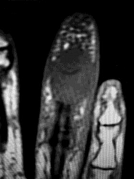

A 55-year-old woman feels a 'pop' in the back of her knee while squatting. An MRI is shown:

A posterior horn medial meniscus root tear is identified. Biomechanically, a complete medial meniscus posterior root tear alters contact pressures to a degree equivalent to which of the following?